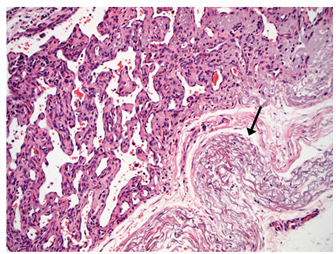

In the two horses diagnosed with conjunctival angiosarcoma, the histopathological findings reflected malignant conjunctival neoplasms that were poorly differentiated with regards to lineage. Both of these neoplasms had a solid epithelioid growth pattern and an absence of vascular channel formation, but vascular lineage was suspected given the location and H&E morphology of the tumour, accompanying perivascular lymphonodular aggregates and absence of overlying surface epithelial pathology with regards to dysplastic or neoplastic changes to indicate carcinoma (Fig. 6). IHC was performed in these two cases in an attempt to rule out the differential diagnosis of carcinoma and confirm vascular lineage as a requirement for further tumour identification (Fig. 7).

Fig. 5. H&E photomicrograph (100× magnification) of case 2 bulbar conjunctival haemangiosarcoma from a horse characterised by irregularly branching, blood-filled vascular channels. There is evidence of solar elastosis in the conjunctival stroma (arrow).

Fig. 8. (A) Case 2 gross pathology photomicrograph revealing the lobulated presentation and red colour to the cut surface. (B) Case 2 low-power histopathology photomicrograph revealing the well-differentiated haemangiosarcoma with blood-filled vessels, note the invasive nature of the tumour tissue (black arrow).

In Figure 8, a conjunctival haemangiosarcoma displays the more “classical” gross appearance of haemangiosarcoma; an exophytic mass with red appearance to both the cut surface and on histopathology. Blood-filled channels lined with neoplastic cells provide the tumour with a red appearance. Although clinically appearing as a discrete mass, the invasive nature of this tumour type can be seen with neoplastic cells infiltrating the cornea outside the mass. Contrast this to Figure (6), a poorly differentiated, solid angiosarcoma. Whilst still marginally exophytic, the gross appearance was cream/pale coloured, and histopathology revealed a lack of blood vessels. The tumour was solid in appearance with poorly differentiated cells making classification difficult. This highlights the importance of haemangiosarcoma as a differential for conjunctival masses in a horse, even if their appearance is not grossly red.